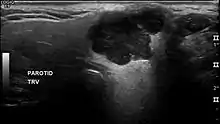

In terms of imaging studies, ultrasound can determine and characterize superficial parotid tumors. Certain types of salivary gland tumors have certain sonographic characteristics on ultrasound.[6] Ultrasound is also frequently used to guide FNA or core needle biopsy.